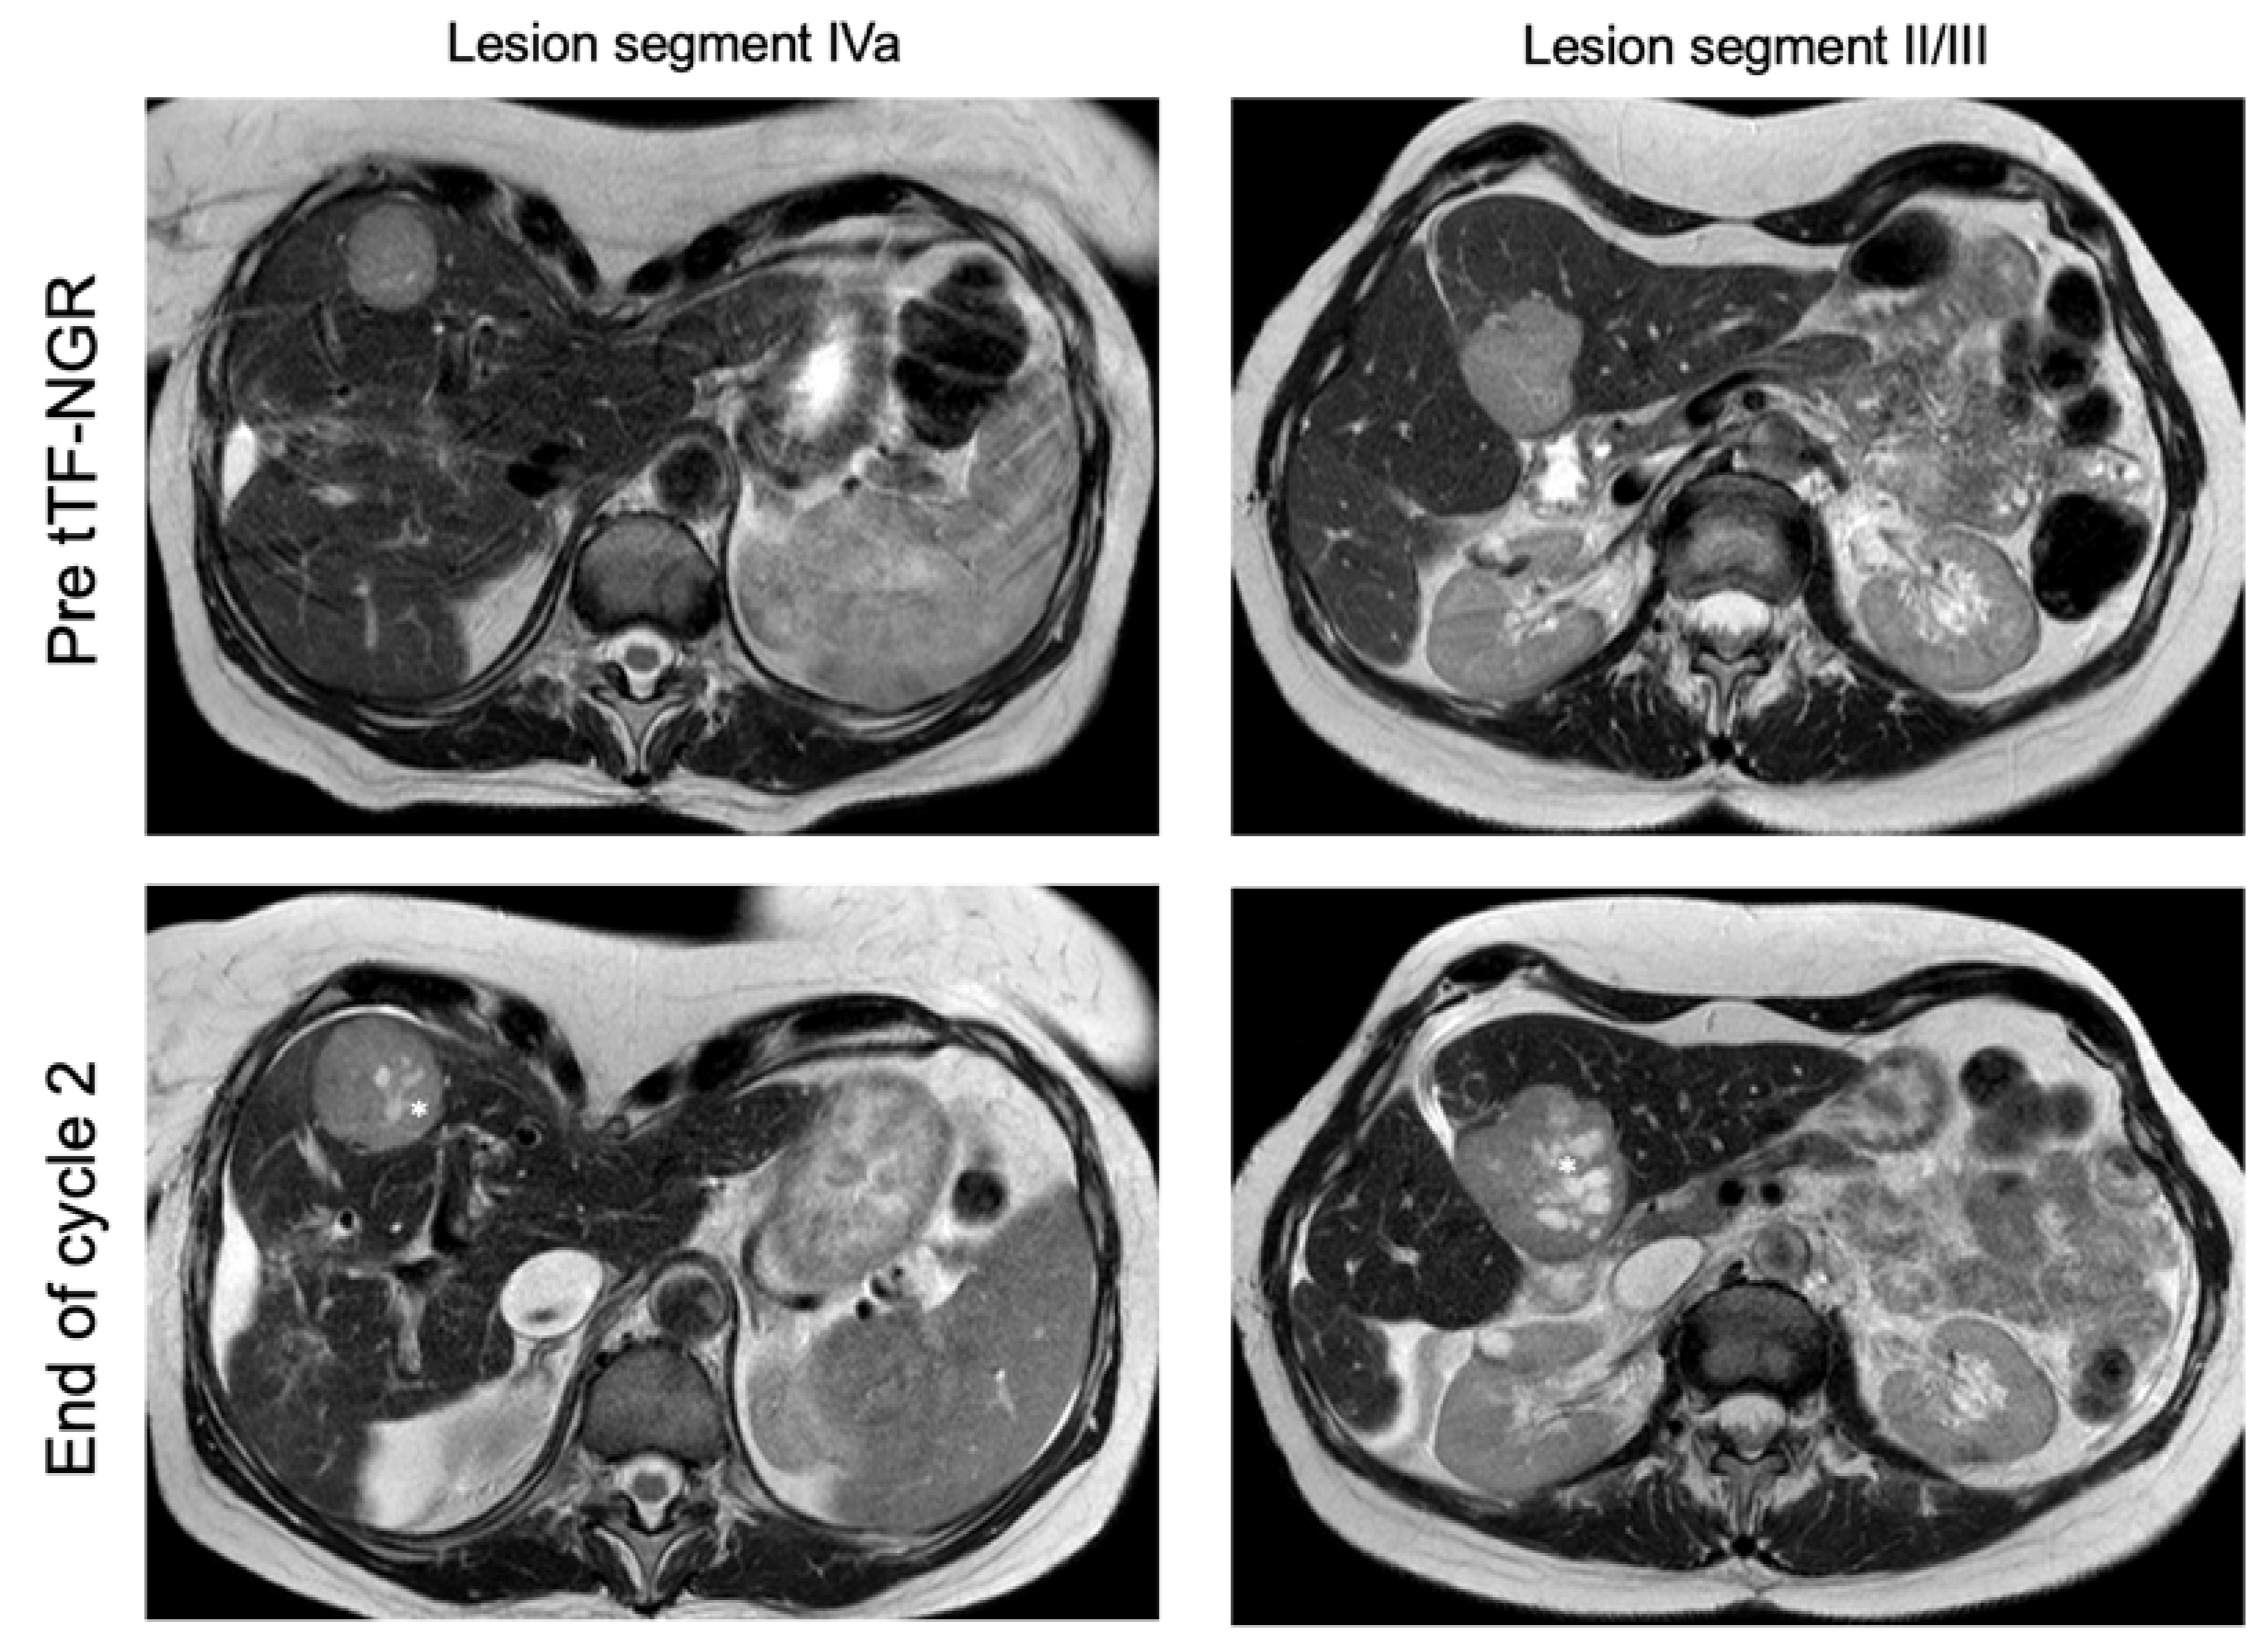

2.4. Dynamic Contrast-Enhanced (DCE) Magnetic Resonance Imaging (MRI)

| 003 | m | 22 | metastatic non-seminomatous germ cell tumor | PEI, HD-PEI, surgery, TI, TIP, HD-CE, Gem/Ox, Radiation, Nivolumab | 2 | cycle 1: 1.0 cycle 2: 1.5 | good tolerability, no DLT | I: hemorrhagic/necrotic areas in liver lesions upon therapy (MRI) O: RECIST PD; Q: n.c. |

| 022 | f | 56 | hepatocellular carcinoma, metastatic | TACE, SIRT, Sorafenib (toxicity), Nivolumab (toxicity) | 2 | cycle 1: 3.0 cycle 2: 3.0 | good tolerability | I: hemorrhagic/necrotic areas in liver lesions upon therapy (MRI) O: RECIST PD; Q: n.c. |